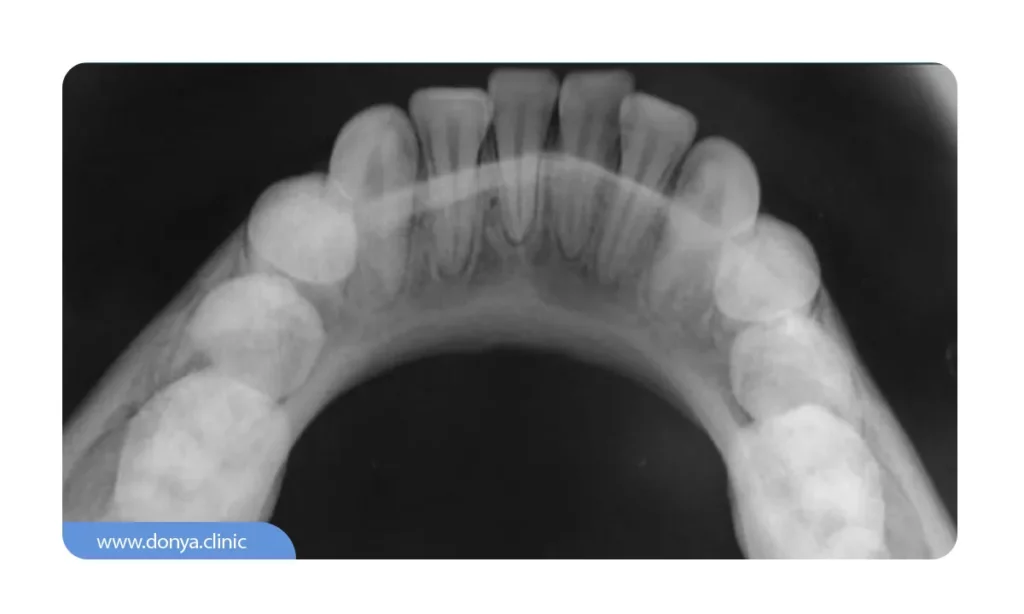

4️⃣ عکس دندان Occlusal (تصویربرداری اکلوزال)

تمرکز تصویربرداری اکلوزال بر روی ناحیه جونده واحدهای دندانی می باشد. نسبت تصویر اکلوزال در مقایسه با دیگر عکس های رادیوگرافی دهان بزرگ تر است. دندانپزشک از طریق عکس Occlusal به بررسی نحوه رشد و رویش دندان های شیری و دائمی گروه های مختلف سنی کودکان می پردازد. لازم است تا بدانید که این تصویربرداری دهان به نمایان شدن ظاهر سقف قوسی شکل فکین فوقانی و تحتانی می پردازد..

💵 قیمت عکس دندان اکلوزال در سال 1404 از 95 الی 120 هزار تومان در مراکز دولتی و 120 الی 144 هزار تومان در مراکز خصوصی تخمین زده می شود.